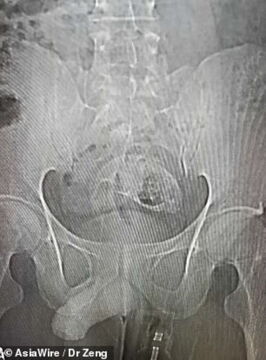

The fish left the mystery sitter with'intense abdominal pain' that lasted over an hour prompting him to visit the hospital. The man had truly gotten the fish stuck up there as scans show just how tight of a squeeze it would have been to get it out.

Initially, thefish enthusiast had to be put in for an endoscopy but attempts to retrieve the Mozambique tilapia were all in vain as the fish was simply too big to come out. The doctors didn't state just how big the fish was but the species reaches 30-40cm on average.